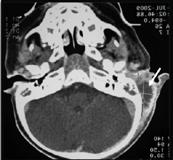

Le tableau clinique initial faisant évoquer une mastoïdite, l’enfant est adressé aux urgences pédiatriques.

Le scanner des rochers montre un comblement complet de l’oreille moyenne et des cellules mastoïdiennes à droite sans abcès sous-périosté, sans condensation, lyse osseuse ou thrombose veineuse.

La numération formule sanguine était normale et la CRP à 11 mg/litre.

Devant le bon état général et après avis des ORL, l’enfant est rentré à domicile sous amoxicilline per os avec une posologie majorée à la dose de 150 mg/kg/j en 3 prises pour une durée de 14 jours au total. L’évolution a été rapidement favorable.

Le scanner injecté des rochers confirme le diagnostic et recherche d’éventuelles complications

Devant une suspicion clinique, l’enfant doit être adressé aux urgences afin de réaliser un scanner injecté des rochers pour confirmer le diagnostic et dépister les complications :

● extra-crâniennes (abcès sous-périosté, paralysie faciale, lyse osseuse, labyrinthite aigue, ostéomyélite, abcès cervical),

● intracrâniennes (thromboses veineuses, empyème cérébral, méningite).

La complication la plus fréquente est l’abcès souspériosté (2,4). La lecture des images peut être difficile. Ne pas hésiter à les revoir ou à demander un avis spécialisé.

◄ Abcès sous-périosté